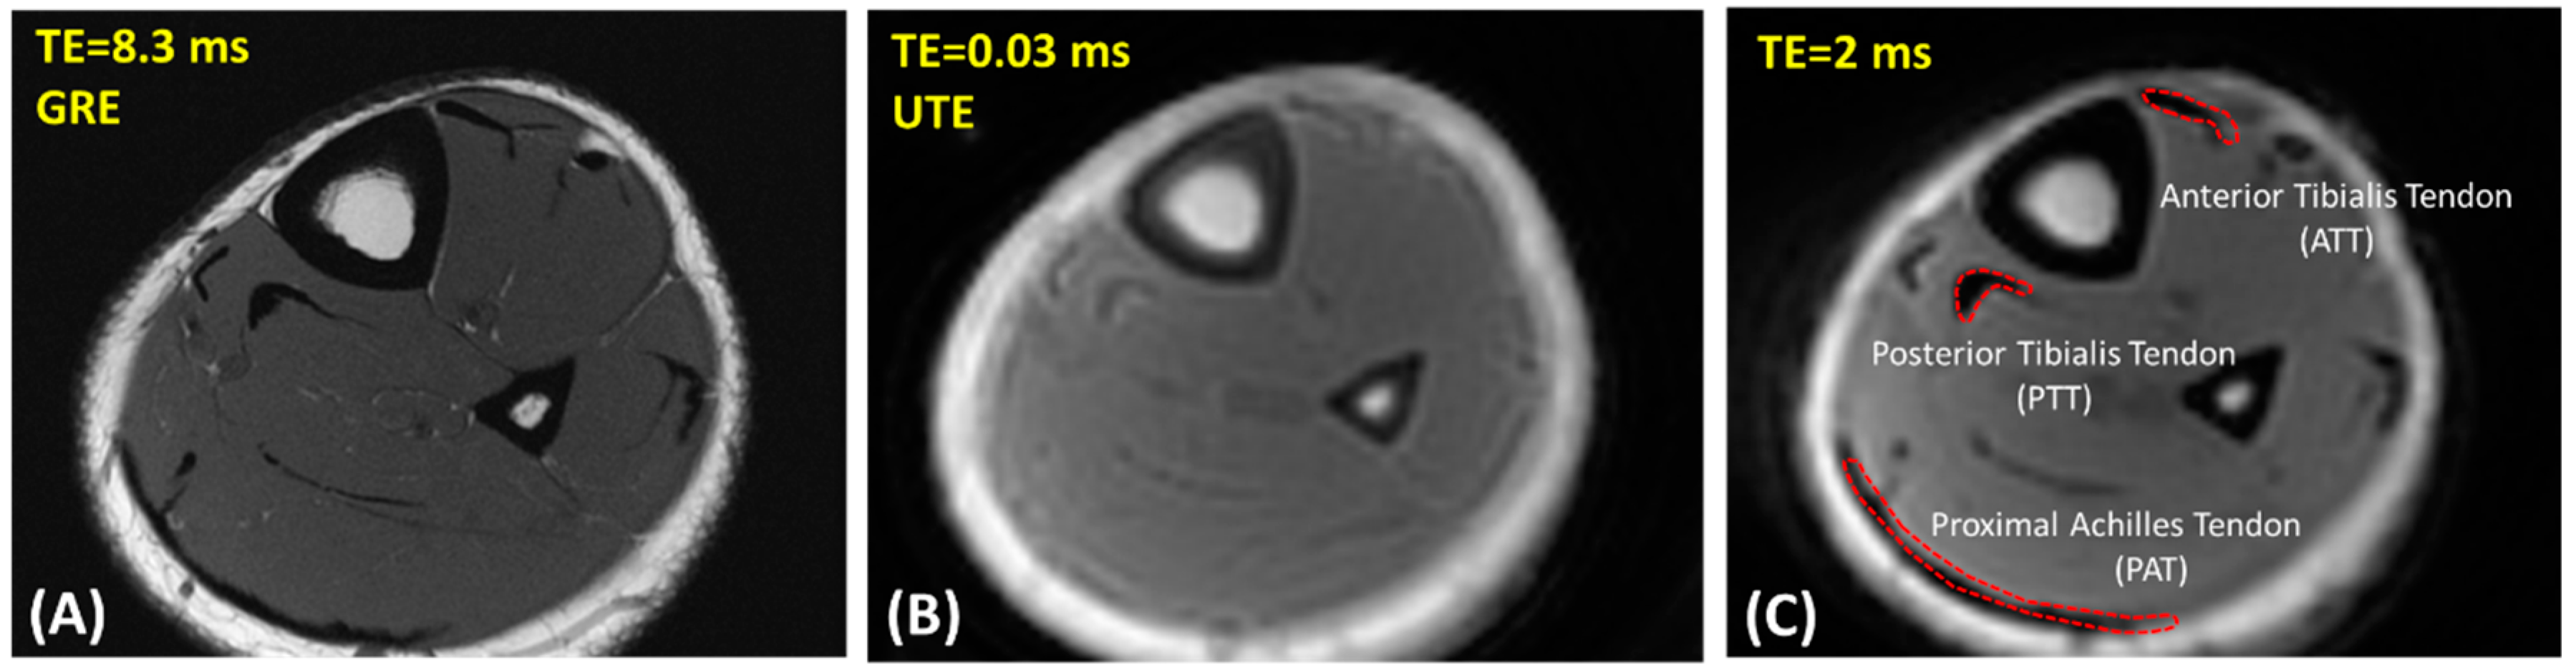

2.2. UTE-MRI Scanning

2.3. Data Analysis